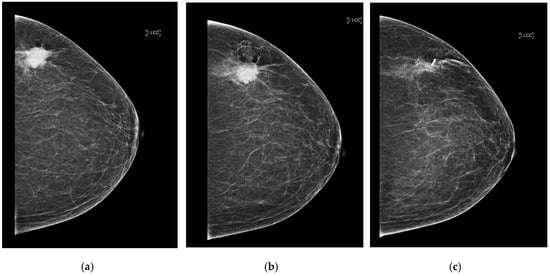

After placement, standard two-view mammograms were obtained to confirm RFID tag placement. Placement accuracy was recorded by measuring the shortest distance, on either the mediolateral oblique (MLO) or craniocaudal (CC) view, from the RFID tag to the intended target (e.g., target lesion, distortion, MCC) on the post-clip mammograms. Following surgical excision, a specimen radiograph was performed to confirm RFID tag presence and location (Figure 3a–c and Figure 4). Additionally, any cases of RFID tag migration were documented, along with factors such as hematoma formation or lesion characteristics that may have influenced RFID tag positioning. Data collection was conducted in compliance with institutional ethical guidelines, ensuring patient confidentiality and adherence to research standards.

Figure 3. (a) Craniocaudal (CC) view of the left breast of predominately fat density (BI-RADS A). There is a 27 mm malignant-appearing mass in the upper portion of the left breast. (b) CC post-biopsy mammogram shows the marker clip within the center of the lesion. Following ultrasound-guided core needle biopsy and accurate clip placement, biopsy results yielded invasive ductal carcinoma (grade 3). The patient underwent neo-adjuvant chemotherapy followed by radiofrequency RFID tag localization. (c) CC view of the left breast. The known mass within the upper outer quadrant has reduced in size following neo-adjuvant chemotherapy and measures 19 mm (from 27 mm initially). The post-localization mammogram shows successful RFID tag placement (at the lateral aspect of the lesion).